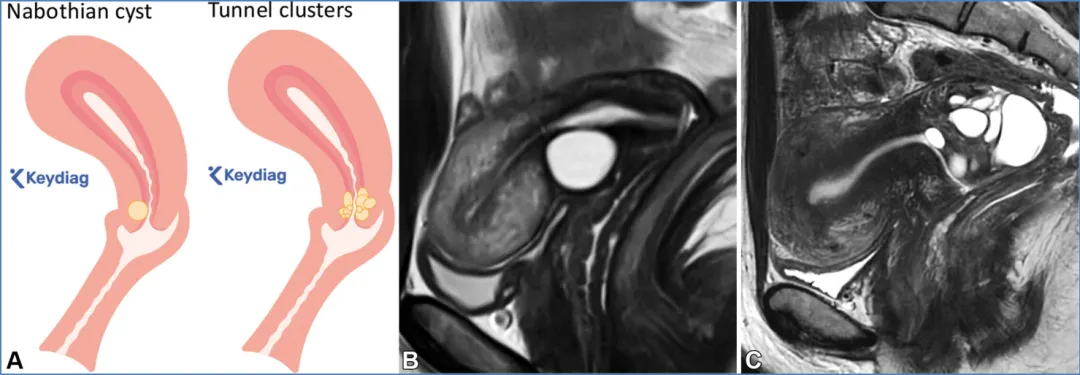

卵巢——卵巢是可活动的腹膜内器官,由卵巢韧带(连接卵巢与子宫角)、卵巢系膜(将卵巢固定于阔韧带)和悬韧带(连接卵巢与盆腔侧壁并包裹性腺血管)支撑(图6)(36)。性腺动脉起源于肾动脉下方的腹主动脉;右侧性腺静脉汇入下腔静脉,左侧性腺静脉汇入左肾静脉。性腺静脉直径大于0.8厘米为异常,尽管性腺静脉直径与静脉反流之间的相关性较差(37)。性腺血管走行于腰大肌前方、输尿管外侧。 卵巢的表现随月经周期阶段和绝经状态而变化。绝经前卵巢为较大的椭圆形结构,在T2加权成像上能清晰显示分区解剖结构,包括T2低信号的皮质、T2等信号的髓质(含疏松排列的基质和血管)、T2高信号的薄壁卵泡,偶尔可见黄体(19,38)。黄体因有黄素化的卵泡膜细胞而呈现T2等信号的厚壁,在退化过程中会变得锯齿状。非出血性黄体中央呈T1低信号、T2高信号,而出血性黄体中央呈T1和T2高信号,有时可见血细胞比容平面。静脉注射对比剂后,卵巢皮质和基质轻度强化,强化程度低于子宫肌层,而黄体壁则表现为早期明显强化(38)。绝经后卵巢比绝经前卵巢小,皮质和髓质呈T2等信号至低信号,偶尔可见小囊肿(38)。表S2以及图7-10详细描述了常见的生理性和其他良性卵巢表现的MRI特征(19,38-42)。图7. 两位不同患者的正常经前卵巢,突出显示了生理学观察结果。(A)示意图显示了带有卵泡的经前卵巢。(B)一位27岁女性患者的轴位T2加权图像显示一个椭圆形卵巢,具有T2低信号皮质(箭头)、T2等信号髓质(白色*)和多个T2高信号卵泡(黑色*)。(C、D)一位30岁女性患者的轴位T2加权(C)和对比增强脂肪抑制T1加权(D)图像显示了黄体(CL),这是经前女性常见的生理学表现。其影像学表现随发育阶段而变化。典型的黄体在T2加权成像上表现为囊性结构,中心呈高信号,壁厚且呈锯齿状,信号强度中等(C中的箭头),在静脉注射造影剂后明显强化(D中的箭头)。图8. 一名34岁闭经女性患者的多囊卵巢综合征与继发性非典型子宫内膜增生。(A)示意图展示了多囊卵巢,这是一种常见的内分泌疾病,影响高达10%的育龄女性。多囊卵巢综合征的诊断依据Rotterdam标准,该标准要求满足以下三项中的至少两项:多囊卵巢、月经稀发或无排卵,以及高雄激素血症。多囊卵巢的定义为:至少一侧卵巢的体积达到10毫升或以上,或者每个卵巢有20个或更多的卵泡(详见表S2)。(B)轴位T2加权图像显示双侧多囊卵巢增大,中央为T2等信号基质(小*),周围有多个T2高信号卵泡。(C)矢状位T2加权图像显示子宫内膜腔内呈不均匀的T2等信号(大*),对应活检证实的非典型子宫内膜增生。在所有增强后序列(包括延迟图像,未显示)中,非典型子宫内膜增生的强化程度低于子宫肌层,这与子宫内膜癌的强化模式相似。图9. 一名27岁女性患者的右侧卵巢扭转,该患者表现为急性盆腔疼痛。轴位T2加权图像显示右侧卵巢(RO)增大且水肿,伴有外周卵泡(箭头所示)。与正常的左侧卵巢(*)相比,右侧卵巢位置异常,位于子宫(U)的中央后方。卵巢扭转的其他表现(未显示)可能包括血管蒂扭转以及强化程度不一,这取决于缺血程度或是否存在梗死。图10. 一位43岁女性患者的输卵管卵巢脓肿,该患者在子宫内膜活检后出现恶心、呕吐和盆腔疼痛症状。轴位T2加权像(A)和对比增强脂肪抑制T1加权像(B)显示左侧附件区有一个多房囊性肿块。该肿块内含有脓性液体,在T2加权像上表现为不同的信号强度(A中的*),并具有增厚的强化壁以及多个强化分隔(B中的箭头)。高b值扩散加权像和ADC图(未显示)显示扩散受限,与脓液的存在相符。经皮引流后获得的细菌培养结果显示大肠杆菌阳性。——输卵管从子宫角延伸至卵巢(39)。近端的壁内部分穿过子宫肌层;远端带有伞端的漏斗部开口于卵巢附近的腹膜腔。输卵管被阔韧带的输卵管系膜包绕(图6)。在MRI上,它们表现为卵巢和子宫之间的T2低信号管状结构。子宫体和宫颈解剖。——子宫由子宫体和宫颈组成,宫颈下段(或子宫颈外口部)突入阴道上部(图2、3)(24、25、43)。在T2加权成像上,绝经前子宫的子宫体(子宫内膜、结合带和外肌层)和宫颈(宫颈管、宫颈内间质和宫颈外间质)均显示出清晰的分区解剖结构。绝经后或接受放射治疗后,这种分区解剖结构会变得不清晰(24、25、43)。子宫内膜腔由均匀的T2高信号子宫内膜衬里,延伸至同样为T2高信号的宫颈管(38)。子宫内膜厚度在子宫矢状面中部沿子宫长轴测量,其数值会随绝经状态和月经周期阶段而变化(表S3)(38、44-49)。对于有绝经后出血的患者,子宫内膜厚度≥5mm为异常;而无症状患者的阈值则不太明确(50)。结合带(子宫内肌层)呈T2低信号,向尾侧延续为T2低信号的宫颈内纤维间质。子宫外肌层呈T2等信号,过渡为宫颈外间质的T2等信号。正常结合带厚度≤8mm,若无微囊肿则可达11mm(45)。 子宫峡部是子宫体与宫颈之间的过渡区,在矢状位T2加权成像上表现为局限性缩窄,在轴位斜向T2加权成像上可见子宫血管进入(图2、3)(24、25)。宫颈内口和外口分别是宫颈管的上下开口。宫颈围绕宫颈管,包括上皮衬里和宫颈间质(43)。宫颈上段由腺状柱状上皮覆盖,宫颈下段(包括子宫颈外口部)由鳞状上皮覆盖。鳞状上皮与柱状上皮的交界处(鳞柱交界)在生育年龄具有动态变化,是大多数宫颈癌前病变和宫颈癌的起源部位。宫旁组织由主韧带和宫骶韧带构成,从宫颈两侧延伸至盆侧壁,包绕子宫血管、神经和输尿管(图2、3)。表S3以及图11-13概述了常见的子宫体和宫颈良性病变的MRI特征(38、44-49)。图11. 一位50岁女性患者的子宫内膜息肉,该患者在乳腺癌切除术后接受他莫昔芬治疗。(A)子宫矢状面示意图显示息肉状子宫内膜病变,伴有因子宫内膜腺体扩张而形成的囊性病灶。(B)冠状斜位T2加权像显示子宫内膜内有一个带蒂病变,具有T2低信号的纤维血管核心(白色箭头)和T2高信号病灶(黑色箭头),这些表现提示为子宫内膜息肉。通常可见明显的强化,与子宫肌层的强化程度相似(未显示)。明确诊断需要宫腔镜下切除,因为子宫内膜息肉、增生和肿瘤可能同时存在,且在影像学特征上可能重叠。偶然可见子宫腺肌症,表现为结合带内存在微囊肿(箭头所示)。图12. 弥漫性和局灶性子宫腺肌病(或子宫腺肌瘤)。(A)子宫矢状面中部的插图显示了弥漫性子宫腺肌病(上图)与局灶性子宫腺肌病或子宫腺肌瘤(下图)的对比。(B、C)两名不同的月经过多患者的矢状位T2加权图像显示,T2低信号的交界区(JZ)弥漫性增厚,伴有散在的T2高信号微囊肿(B中的实线),以及前部交界区伴有微囊肿的局灶性肿块样不对称增厚(C中的虚线)。这些表现是由于子宫肌层内存在异位子宫内膜腺体和间质(微囊肿)以及反应性平滑肌增生(交界区增厚)所致。图13. 纳博特囊肿与隧道簇。插图(A)及两名不同患者的子宫正中矢状面T2加权图像(B、C)显示,浅层宫颈基质内的单房囊肿为典型的纳博特囊肿(A图左图;B图),而向宫颈基质深部延伸的多房囊肿为隧道簇的特征性表现(A图右图;C图)。务必在增强图像上排除强化实性组织的存在(未显示),因为多房性宫颈病变中若出现强化实性组织,应怀疑宫颈胃型腺癌。可能需要进行宫颈锥形活检以明确诊断。子宫在骨盆内的位置会因膀胱充盈程度和盆腔瘢痕情况而有所不同。倾位指的是宫颈与阴道之间的角度:前倾位是向前倾斜,后倾位是向后倾斜(图14)(38)。屈曲描述的是子宫体与宫颈之间的角度:前屈是向前弯曲,后屈是向后弯曲(38)。图14. 插图(A)和磁共振图像(B、C)显示了女性骨盆内子宫的各种位置。子宫倾(Version)指的是宫颈与阴道之间的角度:A中的上组插图将该角度显示为黄线相对于红线的倾斜度。前倾(Anteversion)指向前倾斜,后倾(Retroversion)指向后倾斜。子宫屈(Flexion)描述的是子宫体与宫颈之间的角度:A中的下组插图将该角度显示为蓝线相对于黄线的倾斜度。前屈(Anteflexion)指向前弯曲,后屈(Retroflexion)指向后弯曲。两名患者的矢状位T2加权图像(B、C)中,B显示的是前倾前屈位子宫,C显示的是后倾后屈位子宫。阴道是一个纤维肌性结构,通过膀胱阴道隔与膀胱相隔,通过直肠阴道隔与直肠相隔(图4)(51)。在轴位T2加权成像上,绝经前阴道通常呈H形或W形塌陷,具有高信号的黏膜皱襞和低信号的壁。绝经后,皱襞消失,阴道壁厚度变薄。阴道上部有由突出的宫颈形成的穹窿,阴道下部通过阴道口开口于外阴前庭。表S4和图15详细描述了常见良性阴道病变的MRI特征(51-53)。图15. 四个不同患者的矢状面示意图(A)和轴位T2加权图像(B–E)显示了阴道囊肿、斯基恩氏腺囊肿以及尿道憩室。巴氏腺囊肿:位于耻骨联合处或其下方阴道后外侧壁的单房囊肿(A中的灰色椭圆形,B中的T2高信号囊性病变)。加特纳管囊肿:位于耻骨联合处或其上方阴道前外侧壁的单房囊肿(A中的蓝色椭圆形,C中的T2高信号囊性病变)。斯基恩氏腺囊肿:位于耻骨联合下方、阴道前方、尿道下段外侧的单侧或双侧小单房囊肿(A中的浅黄色椭圆形,D中的T2高信号囊性病变)。尿道憩室:在耻骨联合附近,尿道中远端后外侧出现的圆形、椭圆形或U形T2高信号液性囊袋状突起(A中的尿道囊袋状突起)。在罕见情况下,尿道憩室可能完全环绕尿道(E中的T2高信号环形囊性病变)。外阴由女性外生殖器组成(图16)(53)。阴阜位于耻骨联合前方,由脂肪组织构成。大阴唇是位于阴阜下方并与其相连的厚皮肤皱襞。小阴唇是大阴唇之间较薄的皱襞,向前会合于阴蒂头。小阴唇之间的前庭包含尿道外口(尿道口)和阴道口(阴道开口)。图16. 示意图(A)和轴位T2加权图像(B)显示了外阴区域或女性外生殖器。阴阜位于耻骨联合前方,由脂肪组织构成。大阴唇是位于阴阜下方且与其相连的厚皮肤皱襞。小阴唇是大阴唇之间较薄的皱襞,向前汇聚于阴蒂头。小阴唇之间的前庭前部有尿道外口(尿道口),后部有阴道口(阴道开口)。参考文献:https://doi.org/10.1148/rg.250029